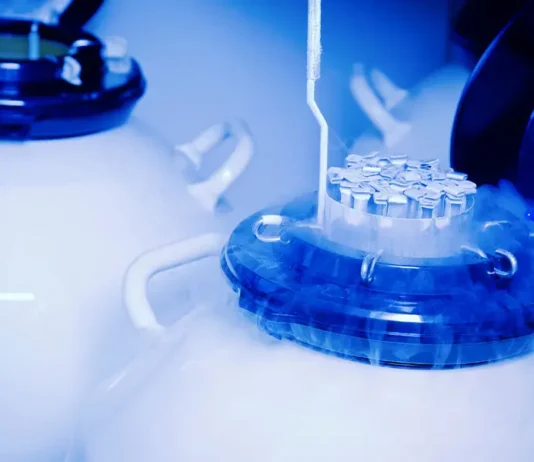

Miscarriage: Safety Measures And Diet You Need To Look On

Have you ever gone through an unpleasant miscarriage in your life? It’s definitely a very heart-breaking situation that puts you down with loads of...

Treatments for Recurrent Miscarriage

Many women have a miscarriage at just once or another. Miscarriages will happen for several reasons. Having a miscarriage doesn’t mean a lady can have another miscarriage if she tries once more. However, some ladies suffer over one miscarriage. This...